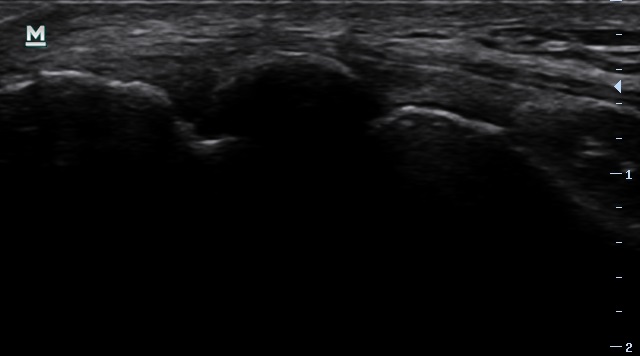

Al hacer Eco nos encontramos algo, lo que parece (en principio, y a la espera de RMN) una calcificación (sombra acústica posterior) de gran tamaño, en comparación con las calcificaciones que se suelen encontrar en tendón extensor. (adjunto 2ª imagen del tendón contralateral sano)

Y para acabar la semana➡️una imagen curiosa d un pcte con dolor lat de codo, tras trauma hace 5 meses. Médico y fisio lo han manejado como una tendinopatía, tratando musc + ej excéntricos, q generan dolor. Con ello no solo no ha mejorado, sino q empeora dolor local e hiperalgesia